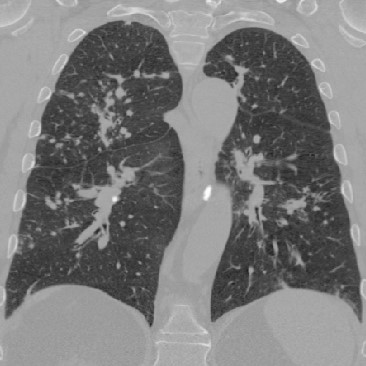

To illustrate the patterns in the radiomic biomarker information obtained across the range of disease, we examine the values from three representative individuals, from healthy, mildly abnormal (Sarc A), and very abnormal (Sarc B) CT scans. As disease becomes more apparent on the CT slices (from healthy to very abnormal) (Figure 1), the values for Moran’s increase. In contrast, the values for fractal dimension and Geary’s C decrease (Tables 3, 4, 5). An increase in Moran’s and a decrease in Geary’s C are indicative of more positive spatial autocorrelation; a decrease in fractal dimension is indicative of smoother structures. The trend in these parameters are clinically important, since we expect to see more positive spatial autocorrelation and smoother structures in CT slices as disease worsens.